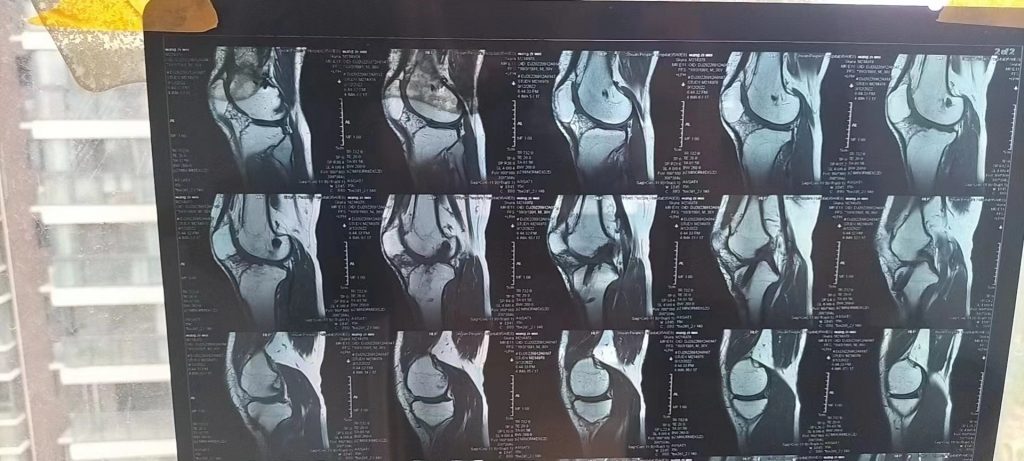

2022年9月12去拍了核磁共振,重建的韧带粗壮清晰,抽屉试验正常。唯一遗憾的是,前叉慢慢失效的过程,股骨撞击髌骨照成股骨滑车位置的软骨缺损,现在有点不适。软骨再生目前很困难,有好的办法叉友医生可以给我点建议,可以在文章底部留言告诉我。